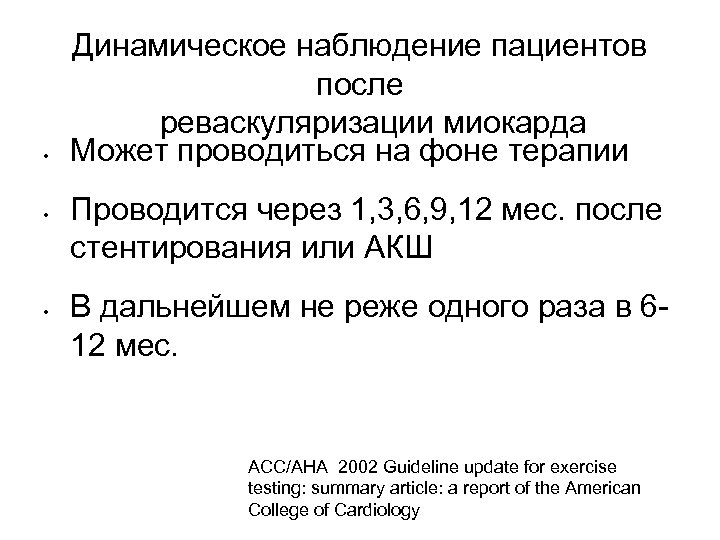

• • • Динамическое наблюдение пациентов после реваскуляризации миокарда Может проводиться на фоне терапии Проводится через 1, 3, 6, 9, 12 мес. после стентирования или АКШ В дальнейшем не реже одного раза в 612 мес. ACC/AHA 2002 Guideline update for exercise testing: summary article: a report of the American College of Cardiology

• • • Динамическое наблюдение пациентов после реваскуляризации миокарда Может проводиться на фоне терапии Проводится через 1, 3, 6, 9, 12 мес. после стентирования или АКШ В дальнейшем не реже одного раза в 612 мес. ACC/AHA 2002 Guideline update for exercise testing: summary article: a report of the American College of Cardiology